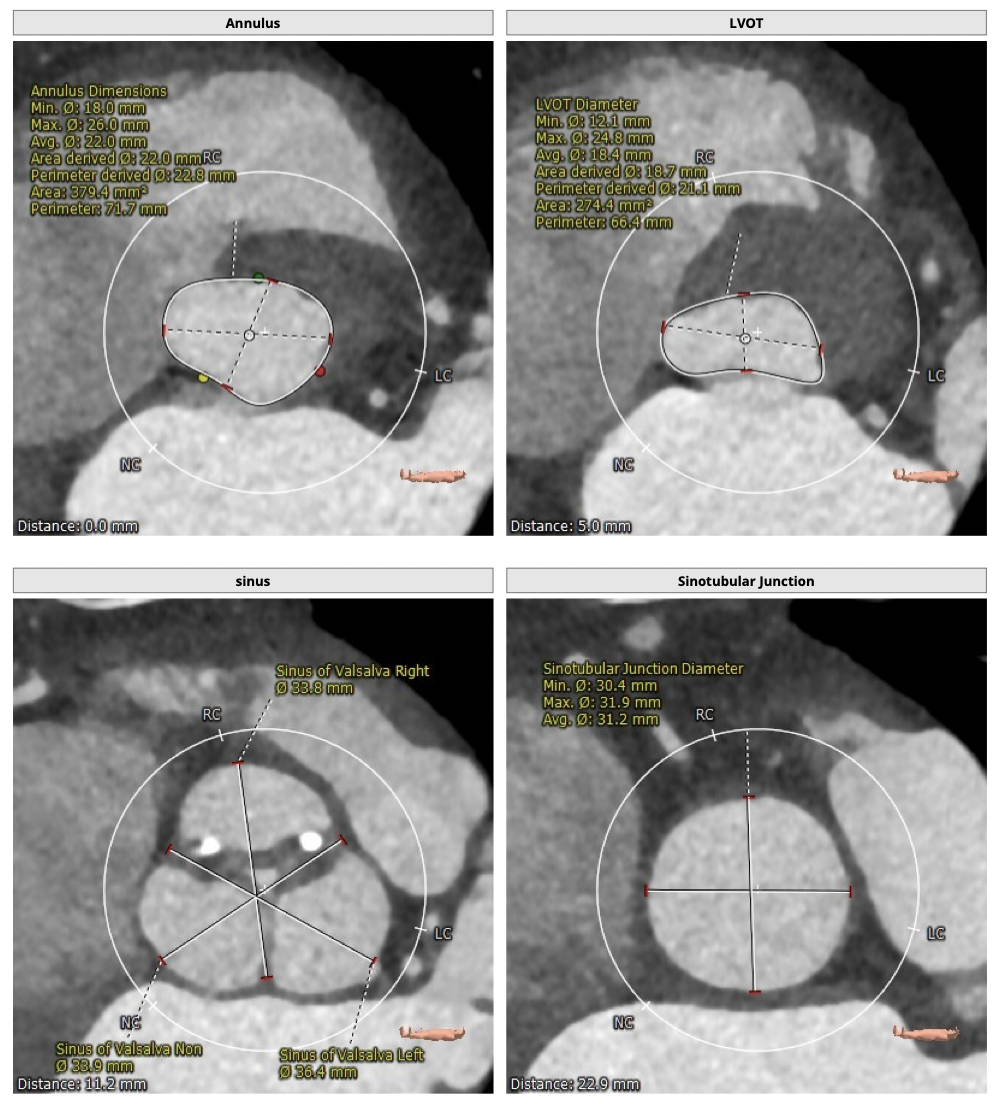

主动脉CT

FEops评估报告

FEops评估瓣周漏

根据FEops量化评估,选用L26瓣膜高位释放会导致8.2ml/s的瓣周漏,而选用L26标准位释放会导致7.4ml/s的瓣周漏,两种释放位置产生的瓣周漏均低于发生中度至重度瓣周漏临界值16ml/s,所以两种释放位置均可以纳入考虑范围,由FEops模拟瓣周漏的3D建模得知发生瓣周漏的主要区域为左右交界处的钙化位置。

L26号瓣膜标准位释放

L26号瓣膜高位释放

FEops评估瓣膜稳定情况

根据FEops评估的L26瓣膜标准位释放结果,发现瓣膜起始位置与稳定位置有较大的改变,判断发生下滑可能性比较大,建议使用VenusA-Plus®可回收输送系统保障手术安全。

难点分析:

*患者为TYPE1型二叶瓣,瓣膜释放后具有一定瓣周漏风险;

*升主动脉明显扩张,术中操作需轻柔;

制定策略:

经分析研判,拟从右侧股动脉穿刺入路,选用L26号的VenusA-Valve瓣膜,采用VenusA-Plus可回收输送系统确保瓣膜的精确释放,瓣膜释放后结合造影和超声情况,决定是否后扩。